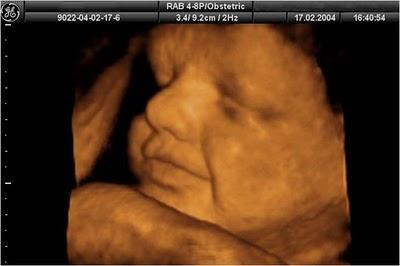

GRACIAS A LA ECOGRAFÍA 4D, EL FUTURO BEBÉ SE MUESTRA,A QUIEN ESTÁ AFUERA EN IMÁGENES DE GRAN NITIDEZ,A SÍ MISMO Y SUS EXPRESIONES FACIALES.